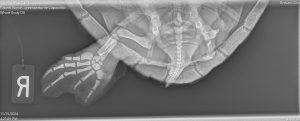

Sea Turtle Healing Center manager Shanon Gann uses the portable generator to take an X-ray of Capocollo.

Each time a sea turtle comes through the doors of our L3Harris Animal Care Center, our dedicated veterinary staff takes ultrasounds and radiographs—or X-rays—of the turtle. These diagnostics help our team navigate the patient’s condition and determine the next steps in treating any injuries or illnesses.

Capocollo is a green sea turtle who has been in our care since February because of a whole assortment of ailments from bone infections to pneumonia, Jess said.

Because our team takes frequent X-rays tomonitor their condition, our new machines certainly come in handy! It’s our hope that we are in the final weeks of Cappy’s treatment before their release.

Capocollo came into our care with only one rear flipper, but this shouldn’t inhibit their ability to swim.

These X-ray machines allow our team to “collimate” or isolate a turtle’s body part to focus on a specific area; This allows us to pinpoint exactly what we’re looking for.